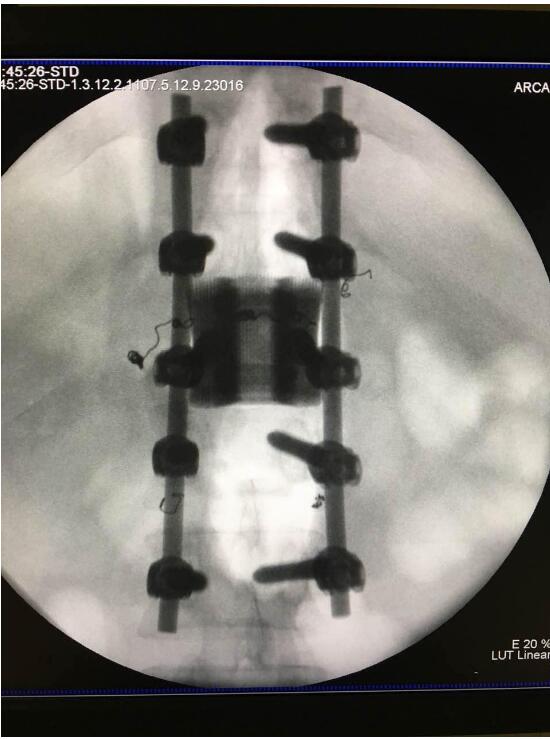

2018年2月7日华钛三维与南方医院脊柱骨外科联合澳大利亚技术科学与工程院吴鑫华院士领导的莫纳什大学增材制造研究中心合作的世界第一例3D打印个性化“人工椎体/椎间盘一体化“植入手术成功实施。不仅保住了病人的脊椎,还保住了其日后的活动能力。

这次手术是广州华钛三维骨科研究中心(华钛三维骨科研究院)与南方医院联合澳大利亚技术科学与工程院吴鑫华院士领导的莫纳什大学增材制造研究中心合作的世界第一例3D打印个性化人工椎体/腰间盘一体化植入手术。南方医院脊椎及骨病外科郑明辉副主任医师在岭南名医陈建庭主任和朱青安教授指导下,与华钛三维工程师陆国赞合作构思设计,澳大利亚莫纳什大学增材制造研究中心主任吴鑫华院士团队进行了一个多月的个性化钛合金3D打印工艺研究,成功打印出符合病人要求的人工椎体/腰间盘一体化植入物。这次手术的成功,标志着中国的3D打印植入物技术在骨科医疗领域达到世界先进水平。

为了更好的完成手术,陈建庭主任、郑明辉副主任医师等骨科专家与华钛三维的3D打印专家从2017年10月份开始筹备该手术。考虑到每一个病人的脊椎形状都存在差异,骨科专家认为用一个现成的标准植入物不大可能匹配病人的生理参数。医学专家和3D打印专家根据病人脊柱的CT扫描数据,为病人的脊柱建立了精准的3D图像。根据这个图像,治疗团队就能够设计并定制出属于病人的个性化植入物。为了使个性化定制的人工椎体与病人椎体之间更好的融合,手术实施前治疗团队先后设计了100多个方案,制作了数十个植入物的术前模型进行研讨。事实证明,手术最终使用的植入物是最适合手术和病人身体情况的。

利用3D打印技术生产出来的人工椎体是完全按照患者的解剖结构完成脊椎结构重建及固定的, 装上一枚精准的、个性化的人工脊椎,患者康复后完全可以正常地生活和工作。过去这种手术常常是使用钛网内填入自体或异体碎骨作为椎体间支撑材料,但钛网一旦移位压迫脊髓,患者就会有瘫痪的风险。这次手术中的脊椎植入物内部具有经过力学优化设计的晶格结构,比传统钛网具有更强的承重力,金属3D打印可以直接制造出这样的复杂结构。

最终在经历近八个小时后,病人的家属终于等到了好消息:人工椎体/椎间盘一体化金属植入物成功植入,手术顺利。由于病人术中出血量小,生命体征平稳,他不用进入ICU观察,直接回到了普通病房。“现在我们都很高兴,成功做出了世界首例人工椎体/椎间盘一体化金属植入物,病人今后可以与常人一样工作和生活。”郑明辉医生说。